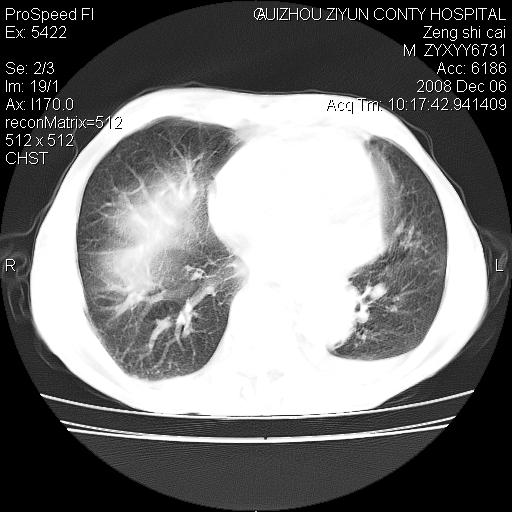

标题: CT16961:M、71岁,咳嗽半年,无血痰;胸片示右肺占位。 [打印本页]

标题: CT16961:M、71岁,咳嗽半年,无血痰;胸片示右肺占位。

右肺癌并纵隔淋巴结及胸膜转移可能性大

右肺纵隔型肺癌伴纵隔淋巴结及胸膜转移!

右肺纵隔型肺癌伴纵隔淋巴结转移!双侧胸水!

1)考虑右肺上叶纵隔型肺癌伴纵隔淋巴结转移。2)心包积液,双侧胸腔积液。

右肺上叶纵隔型肺癌伴纵隔淋巴结转移。心包积液,双侧胸腔积液。